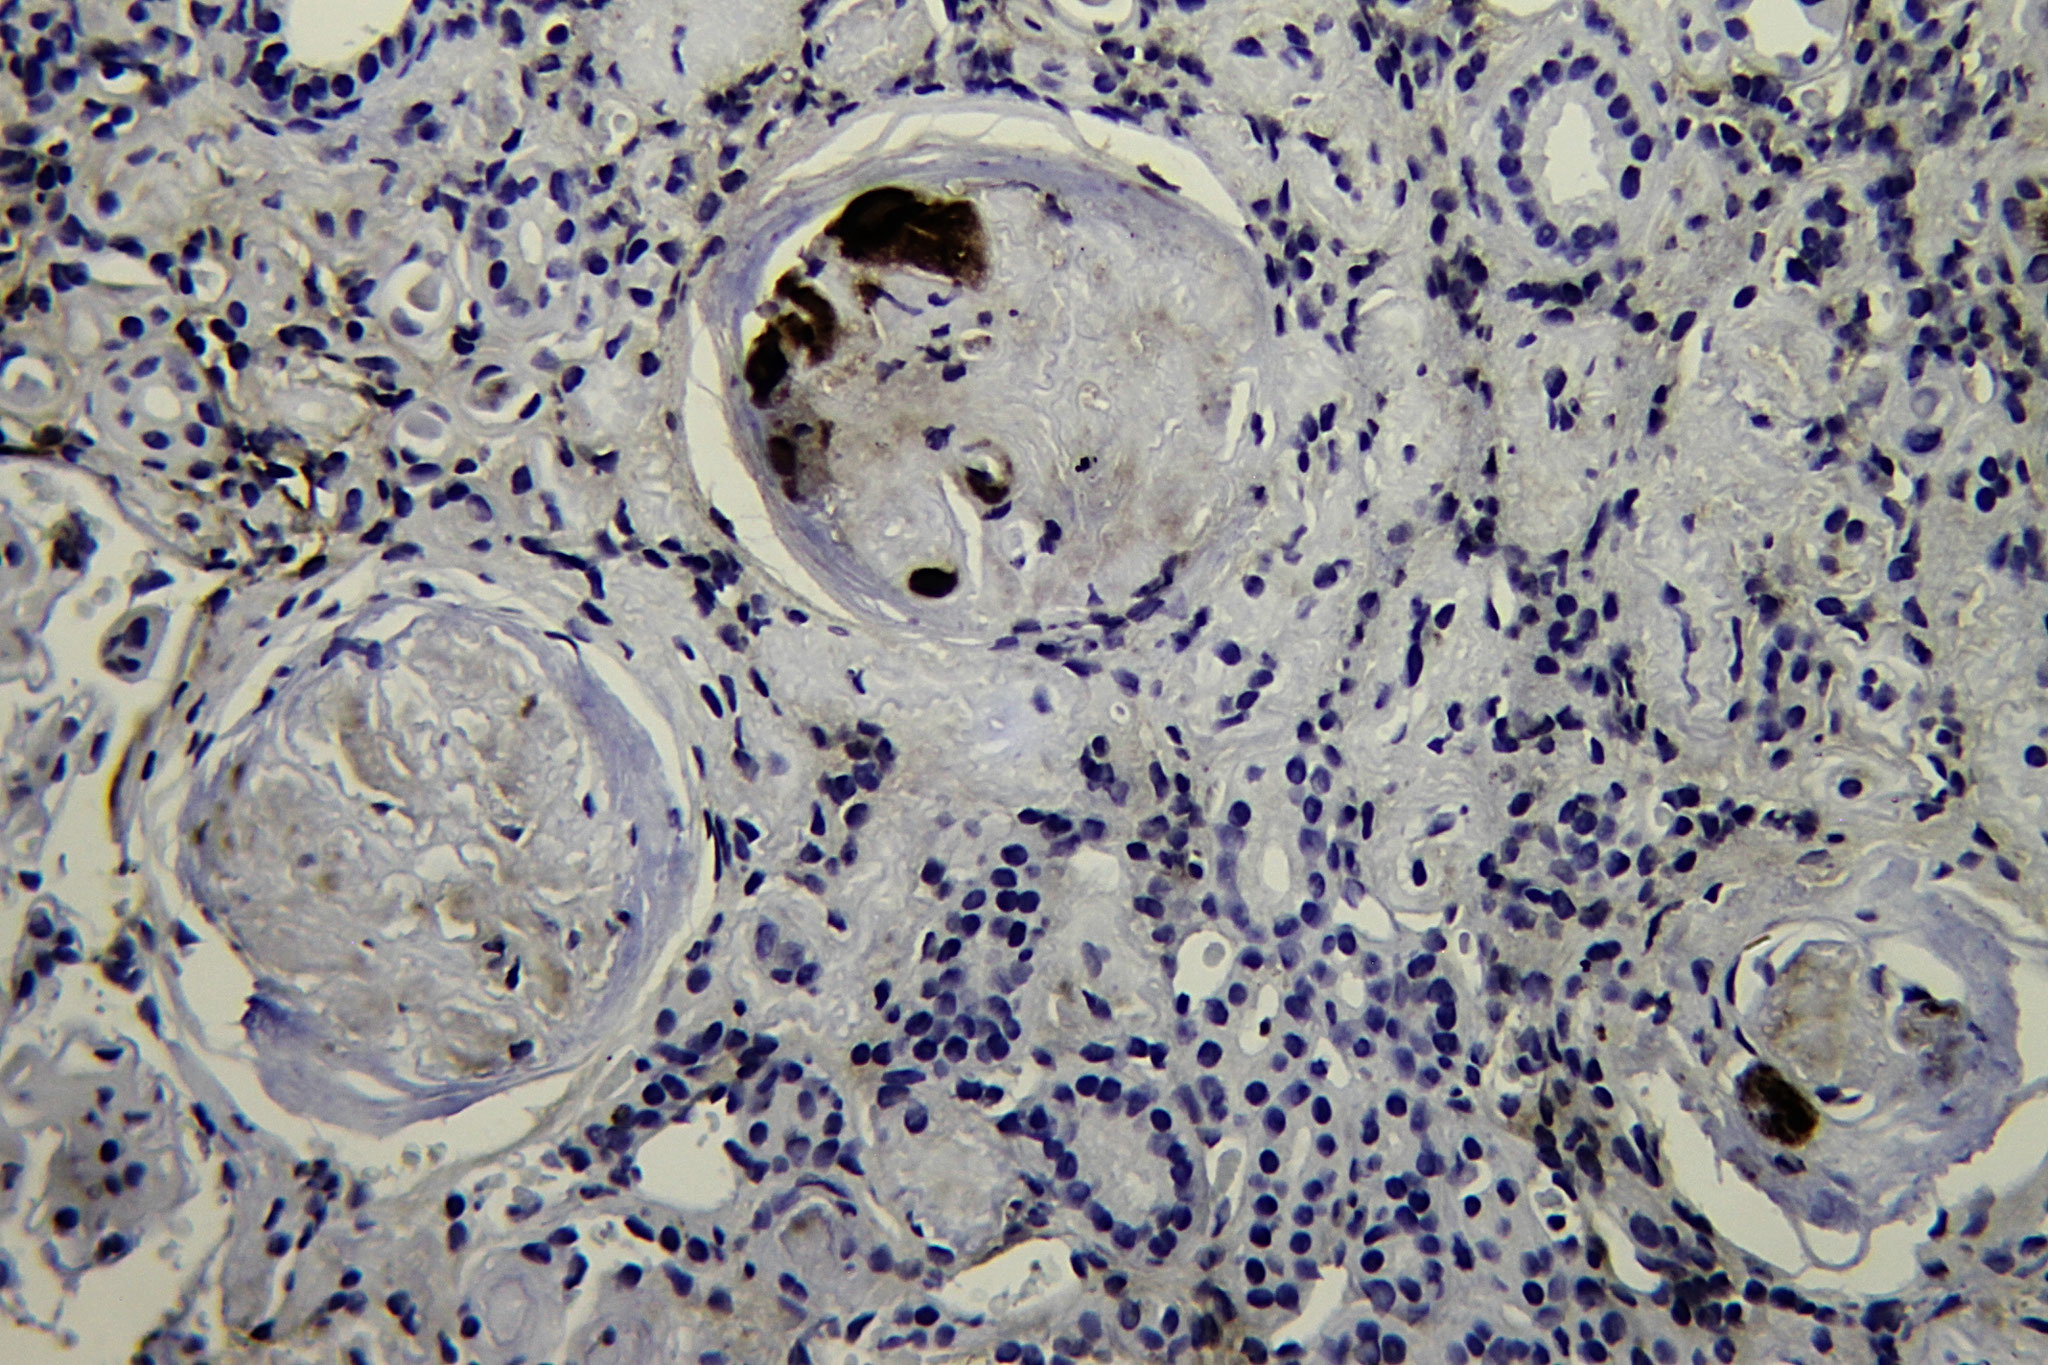

Patología Molecular

El diagnóstico sobre muestras de tejidos y líquidos corporales en plena era de la medicina del futuro, está basado en la integración de técnicas y conocimientos diferentes.

Hoy más que nunca es importante integrar una buena historia clínica con un correcto estudio de imagen y una buena morfología que además puede estar apoyada con proceso especiales complementarios relacionados con la Inmunología, Biología Molecular y Citogenética, generando así un estudio integral conocido como Patología Molecular.